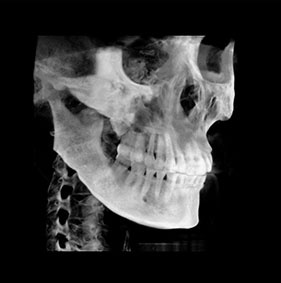

3D CT분석을 통한

정확한 코 재수술

원인 분석

코 재수술은 문제의 원인을

정확한 파악하는 것이 중요합니다.

V브이성형외과의

코성형 전담 의료진은

환자와 면밀한 상담을 통해서

현재 불만족의 원인을 파악하고

개선을 위한 방법을 모색합니다.

3D CT 분석을 통해서 해부학적인 상태를 확인하고,

기존 코수술로 인한 문제를 파악할 수 있습니다.